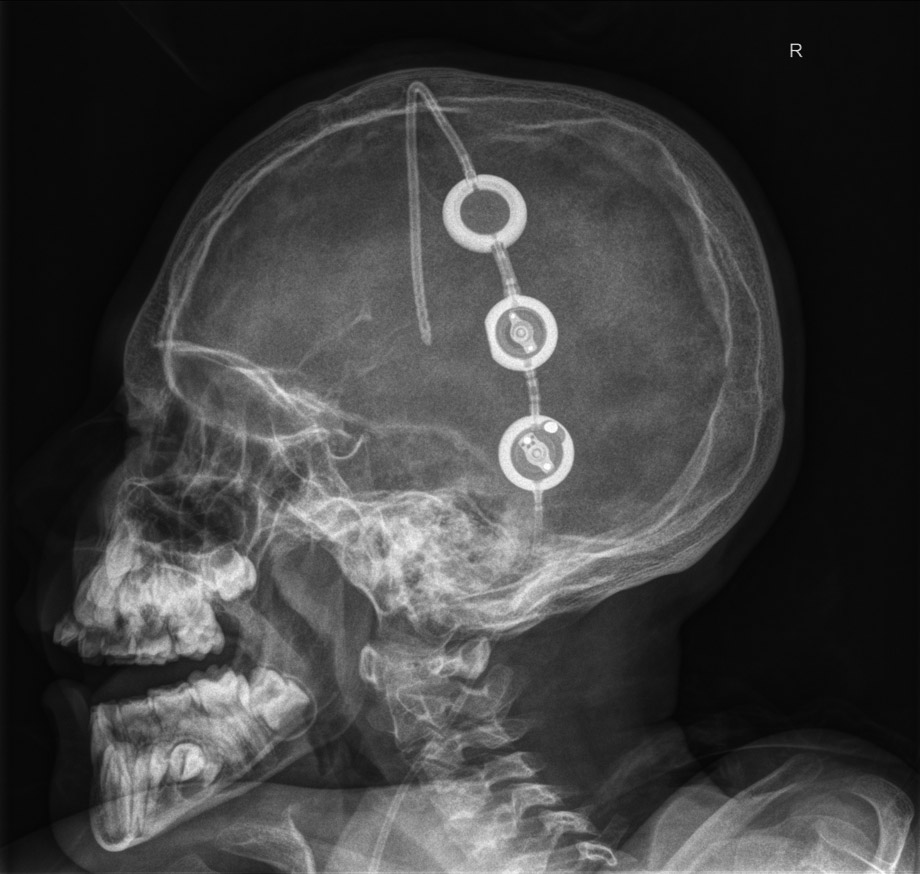

Seitliche Röntgenaufnahme des Schädels eines Patienten, bei dem ein Shuntsystem implantiert worden ist. Das hier sichtbare Ende des Schlauchsystems reicht in die inneren Hirnkammern während das andere Ende bis in den Bauchraum geführt wird (nicht abgebildet) Über die kreisförmigen Ventileinheiten wird der Abflusswiderstand des Hirnwassers reguliert. Foto: Uniklinikum Dresden